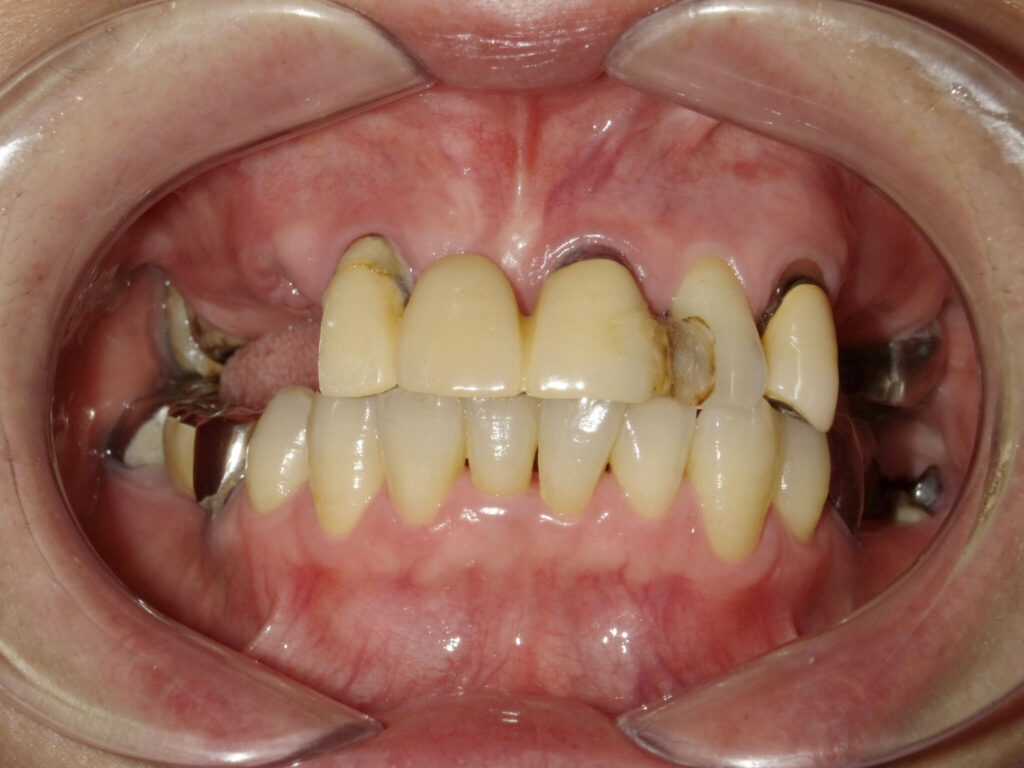

インプラント埋入(左下5・6,右下5・6,左上4・6) サイナスリフト(左上4・6) ジルコニアBr(右上6−左上3) E …続きを見る